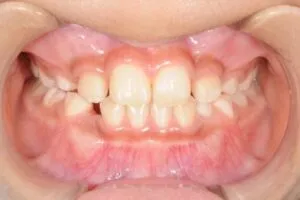

大人になり改善しようとすると全顎的な矯正が必要になりますが

反対咬合用のマウスピースを使用すると

このように改善することができます。

このような咬み合わせになると大掛かりな矯正の治療は必要ないと思います。